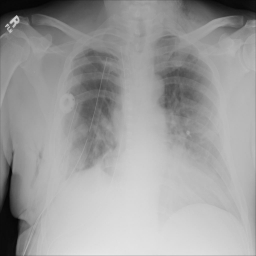

这次比赛的主要任务是从胸部X光图片中判断图片是否含有气胸,如果含有的话分割出气胸。

这次比赛所采用的数据集为胸部X光图片,训练集数目为10675张,第一个阶段测试集数据有1372张。